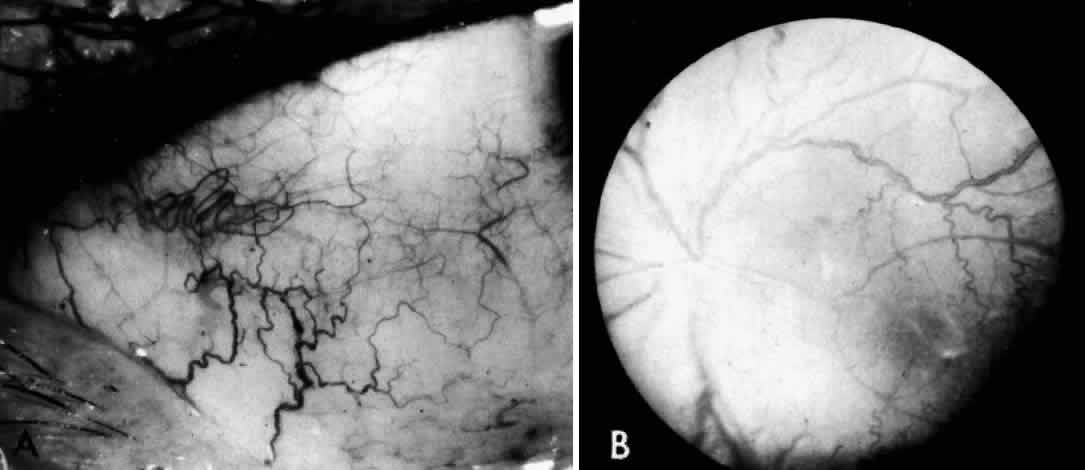

Recognition of the cherry-red spot at the macula is a major diagnostic criterion of Tay-Sachs disease (Fig. 3). It is caused by the accumulation of intracytoplasmic membranous bodies in retinal ganglion cells.

The circular appearance of the fundoscopic lesion reflects the anatomy of the macula. No ganglion cells are present at the very center of the macular region, the foveola, and the central red spot simply represents the normal choroidal background color. The ganglion cell layer surrounding the foveola is several cells thick, and loading of these neurons by storage products results in loss of retinal transparency and a white parafoveal halo. Peripheral to the macular region the ganglion cell layer is only one cell thick, and lipid accumulation in these cells is, therefore, less conspicuous.

Tay-Sachs disease is also the most common storage disease causing macular cherry-red spots (Table 2).3 The variation in the shade of the red spot reflects racial fundus pigmentation. The halo is opaque, slightly elevated, and 1.5 disc diameters in width. The outer border is less sharp than the inner border.

A more widespread opacification of the retina can occur due to involvement of the ganglion cells in the posterior pole. This was observed by Wray4 in a 3½-year-old child with Tay-Sachs disease. The child had black hair and brown eyes, and the cherry-red spot at the macula was brown. The patient was blind, with marked optic atrophy (Fig. 4).

A dynamic process of development of the macular cherry-red spot occurs paralleling the infant's progressive neurologic disorder. The cherry-red spot can be observed as early as 2 months of age and is conspicuous at age 4 to 6 months. Loss of visual acuity may occur without noticeable change in the circular halo. But, in time, the ganglion cells atrophy and optic atrophy and loss of the nerve fiber layer occurs. At this stage blindness coincides.

These deposits are strongly birefringent, and striking macular birefringence may be readily visualized in sections of the retina (Fig. 5) even in the unstained state as well as when lightly stained with cresyl violet or sudanophilic dyes.8 Loss of the ganglion cells and atrophy of the optic nerve, which is also evident, are accompanied by a thinning of the nerve fiber layer.

OCULAR MANIFESTATIONS. By 1984, 24 patients with late-onset GM2-gangliosidosis had been reported but only 4 had macular changes in the form of atypical cherry-red spots, unlike those seen in cases of Tay-Sachs disease. In two of the three cases (cases 4 and 5),25 symptoms began in the late-infantile period (the second year of life). The cherry-red spots were of an unusual nature and described by Brett and colleagues25 as an irregular, poorly defined area of pallor surrounding the fovea. The fovea itself was not clearly demonstrated and was not circular. A photograph of this maculopathy in a blind boy aged 5 years, 8 months (case 4) with onset of the disease at age 14 months is available for comparison with the typical cherry-red spot in classic Tay-Sachs disease.25 The child died at 6 years, 10 months of age. No autopsy examination was made.

The onset of symptoms in four additional cases of late-onset GM2-gangliosidosis was in the juvenile period (the fourth year or later). An atypical cherry-red spot was seen in only one child (case 6) with mild bilateral optic atrophy.25 Cherry-red spots at the macula are not mentioned in previously reported cases of juvenile GM2-gangliosidosis reviewed by Brett and colleagues25 or in the single case studies by Menkes and associates26 but one child showed the beginnings of retinitis pigmentosa 4 years from onset.